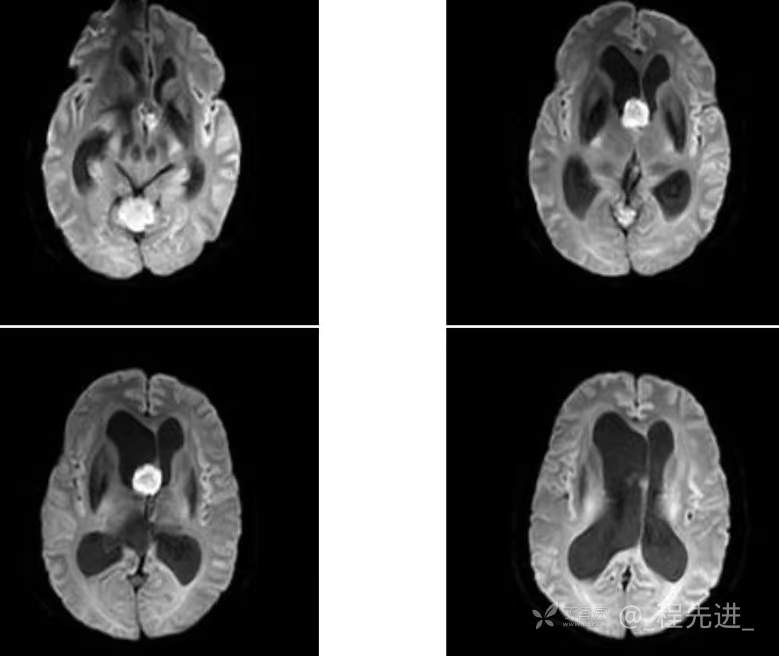

患者性别:女

患者年龄:55岁

简要病史:头痛头晕4年余,无明显诱因,10余年前因“输卵管破裂大出血”手术治疗

辅助检查:实验室检查无特殊